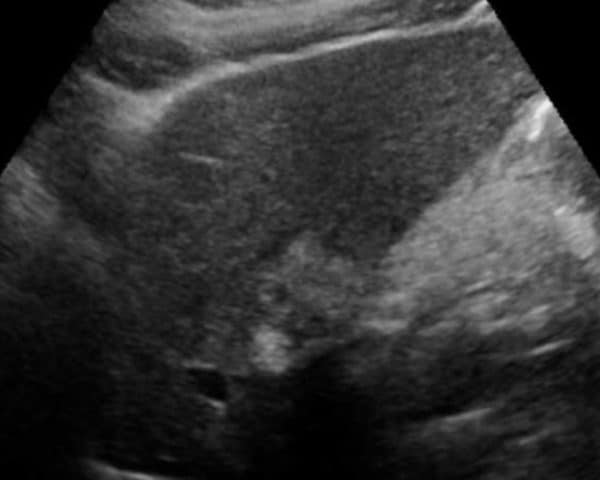

Ung thư đường mật

Ung thư đường mật - Ảnh 4

» Thông tin: Nữ giới – 56 tuổi.

» Lâm sàng: Viêm gan C.